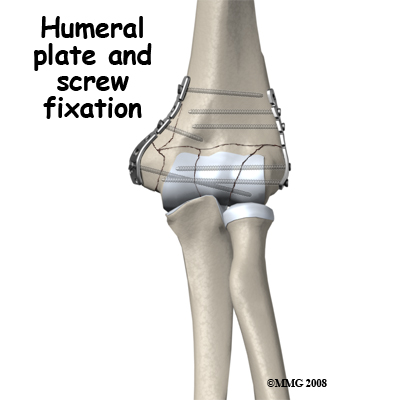

Intra-Articular Distal Humerus Fractures: These are the most challenging fractures of the region to treat. Each fracture is different; however the rationale for most fractures is to restore the joint surface exactly then fix the joint to the shaft of the humerus securely. If the reduction is aligned as anatomically correct as possible it forms a stronger and better fix, but this alignment is not as important as the restoration of the joint surface itself where some inaccuracy is permissible. There are usually pins or screws extending from one condyle to the other, which join the joint fragments, and plates along the columns to fix the joint to the shaft of the humerus.

The fixation should be rigid enough to allow unloaded hinge movement of the elbow joint and rotation of the forearm. The earlier this is achieved, the better it is for the nutrition and recovery of the joint surface. The bone itself takes several months to heal and should not be loaded during this period. Often there are avascular joint fragments that take even longer to heal fully. As the fixation is just beneath the skin, it can be uncomfortable and it is common to remove the fixation once the fracture has healed and good function has been recovered.